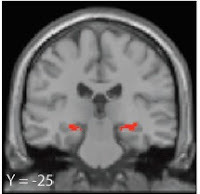

Texas researchers now have shown that learning from exceptions comes from processes originating in the medial temporal lobes, an interesting area of the brain because it's also where episodic memory (memory for personally-experienced events or scenes) lives.